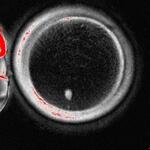

Induction of experimental cell division to generate ...

Scientists use human skin cells to create functional...

生殖研究大突破!皮膚細胞培育出「可受精卵子」,不孕女性、同志伴侶有望受惠 - TNL The News ...

有絲減數分裂

看起來是人工製造出細胞減數分裂的機制